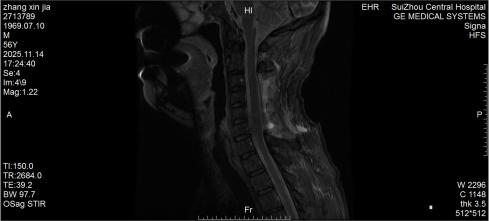

圖1:術(shù)前MRI見椎管內(nèi)積血壓迫脊髓

10月底的深夜,隨州市中心醫(yī)院急診醫(yī)學(xué)科來了一位特殊患者,突發(fā)劇烈頸痛伴雙手麻木,短短3小時(shí)內(nèi)肢體無力逐漸加重,連簡單抬臂都難以完成。脊柱外科團(tuán)隊(duì)緊急評(píng)估后行頸椎磁共振檢查,確診為自發(fā)性頸椎椎管內(nèi)出血—— 這是今年該院救治的第5例同類患者。好在急診手術(shù)及時(shí)清除血腫、解除神經(jīng)壓迫,患者術(shù)后恢復(fù)良好,無任何后遺癥,順利出院。